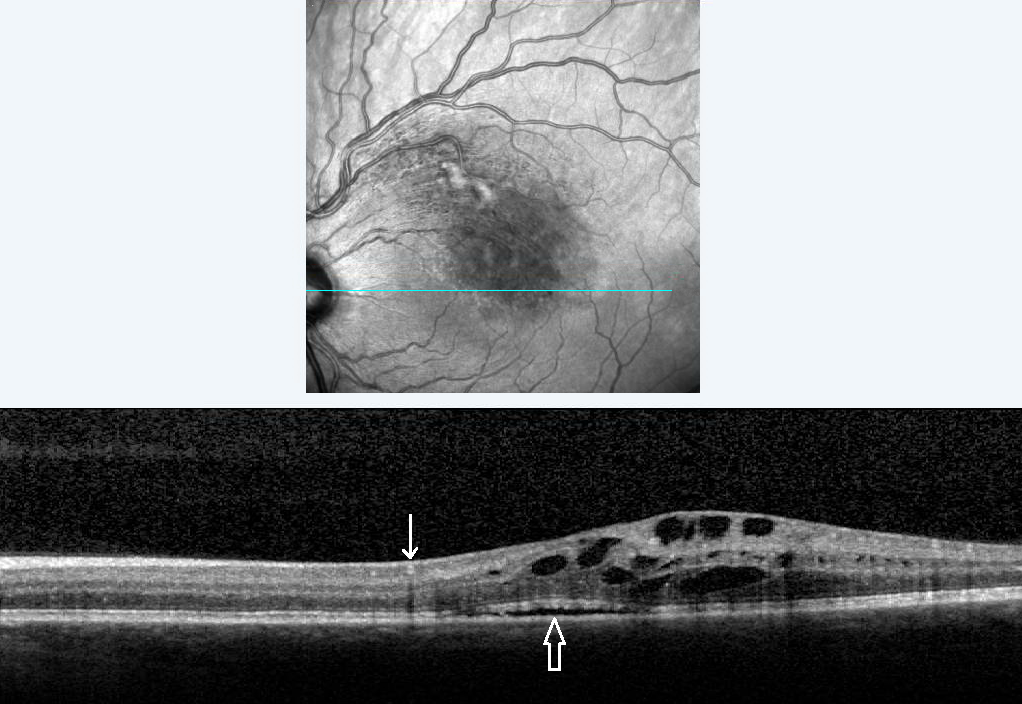

Spectral-domain optical coherence tomography of an eye with a branch retinal vein occlusion (BRVO). A scan of the BRVO reveals cystoid macular edema with intraretinal fluid, and subretinal fluid (open arrow). Intraretinal heme (arrow) appears hyperreflective with a shadow.